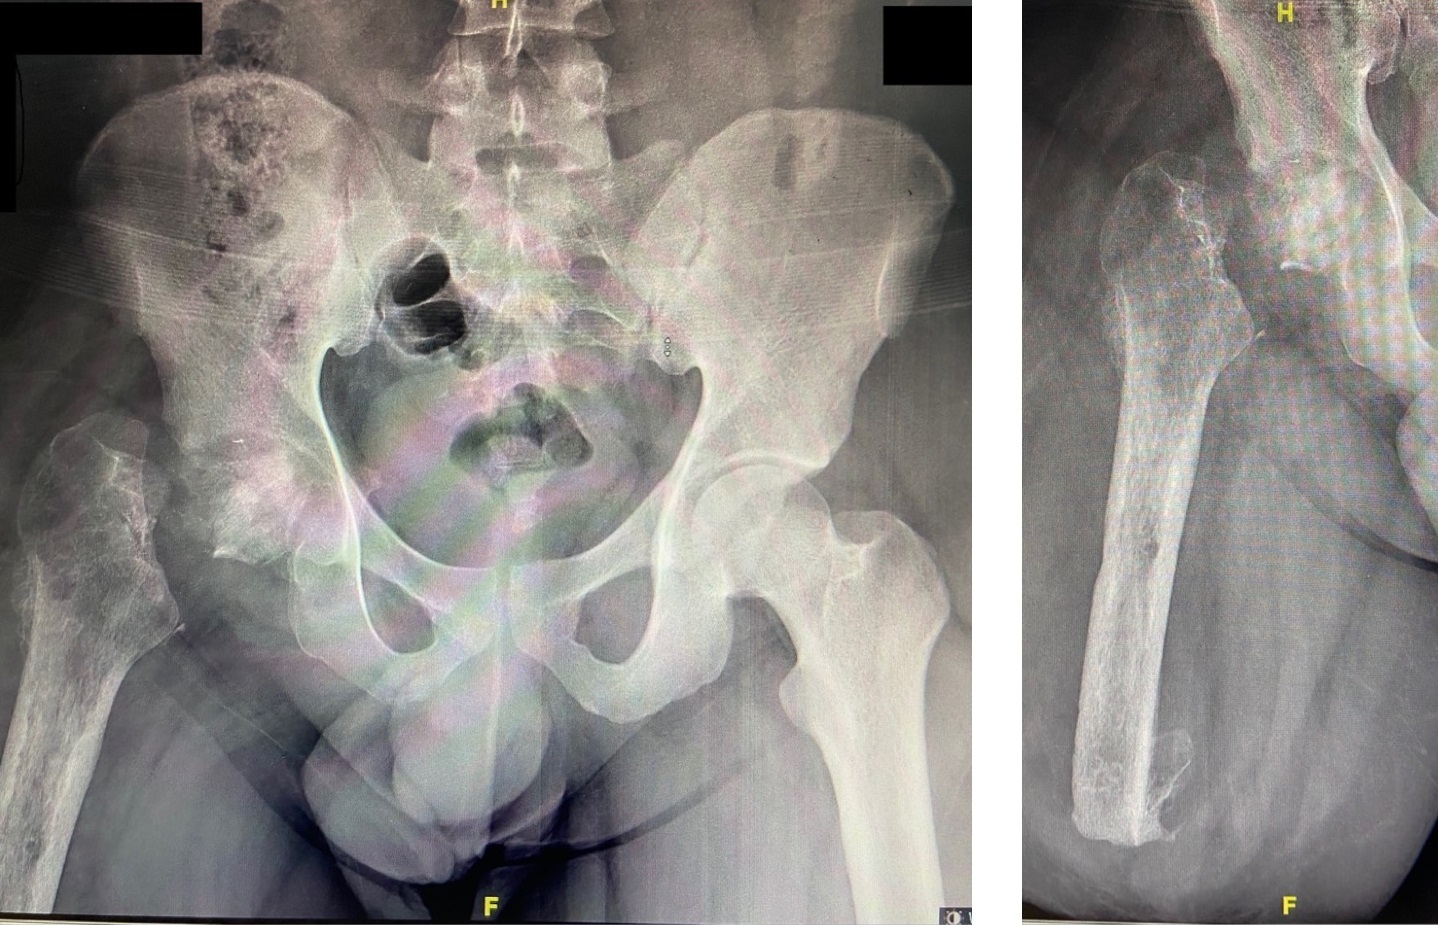

A 22-year-old man presented to our hospital in December 2020 following a motor vehicle accident. The patient had no significant medical, family, or allergy history. He worked in a metal factory and occasionally smoked. The sustained injuries included a closed fracture of the right neck of the femur, an open right supracondylar femur fracture (Gustilo 3C), and an open midshaft fracture of the right tibia (Gustilo 2) (Figures 1, 2, and 3).